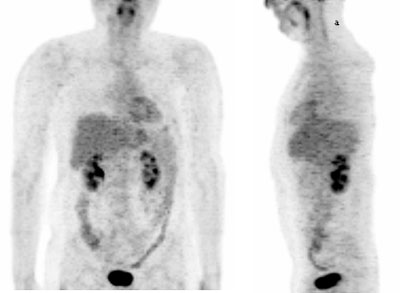

Fig. 3. - Imágenes coronal de tomografía por emisión de positrones de cuerpo completo. Varón de 44 años en estudio por sospecha de linfoma y antecedentes de parotiditis. En el estudio se aprecian diversos focos patológicos en localización iliaca, inguinal, mediastínica y cervical; así como un aumento del metabolismo en ambas parótidas (principalmente en tercio inferior de la izquierda).

1.3 Glándulas salivales y amígdalas Existe un grado de captación de leve a moderado y de carácter simétrico en amígdalas (palatina y lingual), parótidas, tejido linfoide de Waldeyer y glándulas salivares submaxilar y sublingual (fig.3). El grado de captación varía entre las distintas personas, aunque se muestre ligeramente mayor en personas jóvenes.

Es de interés, el conocer si han existido tratamientos o lesiones previas en la zona, que puedan justificar asimetrías en la captación [3 , 17]